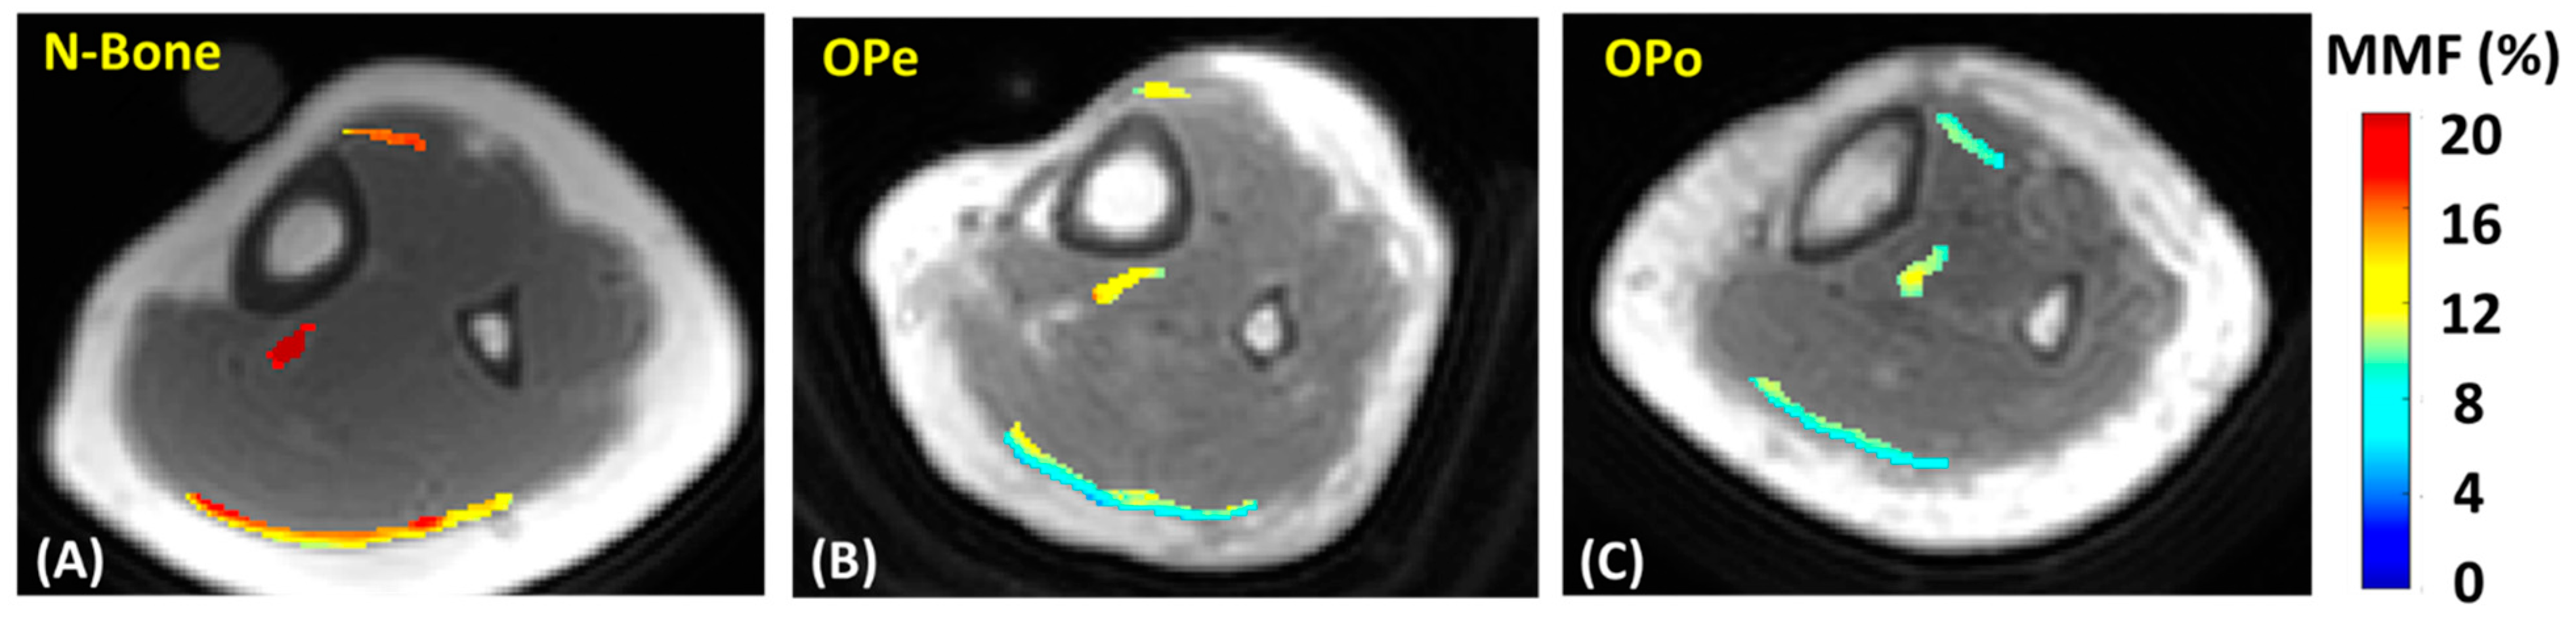

| N-Bone | 829 ± 145 | 733 ± 91 | 698 ± 156 | 758 ± 86 | 16.8 ± 4.7 | 21.0 ± 4.2 | 16.8 ± 3.5 | 18.2 ± 3.6 |

| OPe | 832 ± 144 | 766 ± 101 | 702 ± 111 | 757 ± 99 | 14.3 ± 3.6 | 17.2 ± 3.1 | 15.0 ± 2.9 | 15.8 ± 3.6 |

| OPo | 890 ± 180 | 861 ± 127 | 732 ± 164 | 825 ± 145 | 12.7 ± 2.7 | 14.3 ± 2.6 | 12.4 ± 2.5 | 13.2 ± 2.5 |

| N-Bone Vs. OPe | 0.3 (p = 1.00) | 4.5 (p = 0.70) | 0.7 (p = 0.79) | −0.1 (p = 0.98) | −18.3 (p = 0.03) | −14.6 (p = 0.17) | −10.7 (p = 0.28) | −12.9 (p = 0.17) |

| N-Bone Vs. OPo | 7.3 (p = 0.47) | 17.6 (p < 0.01) | 4.9 (p = 0.67) | 8.7 (p = 0.31) | −32.1 (p < 0.01) | −24.2 (p < 0.01) | −26.1 (p < 0.01) | −27.5 (p < 0.01) |

| OPe Vs. OPo | 6.9 (p = 0.65) | 12.5 (p = 0.06) | 4.2 (p = 1.00) | 8.9 (p = 0.32) | −16.9 (p = 0.07) | −11.3 (p = 0.30) | −17.3 (p = 0.04) | −16.8 (p = 0.02) |